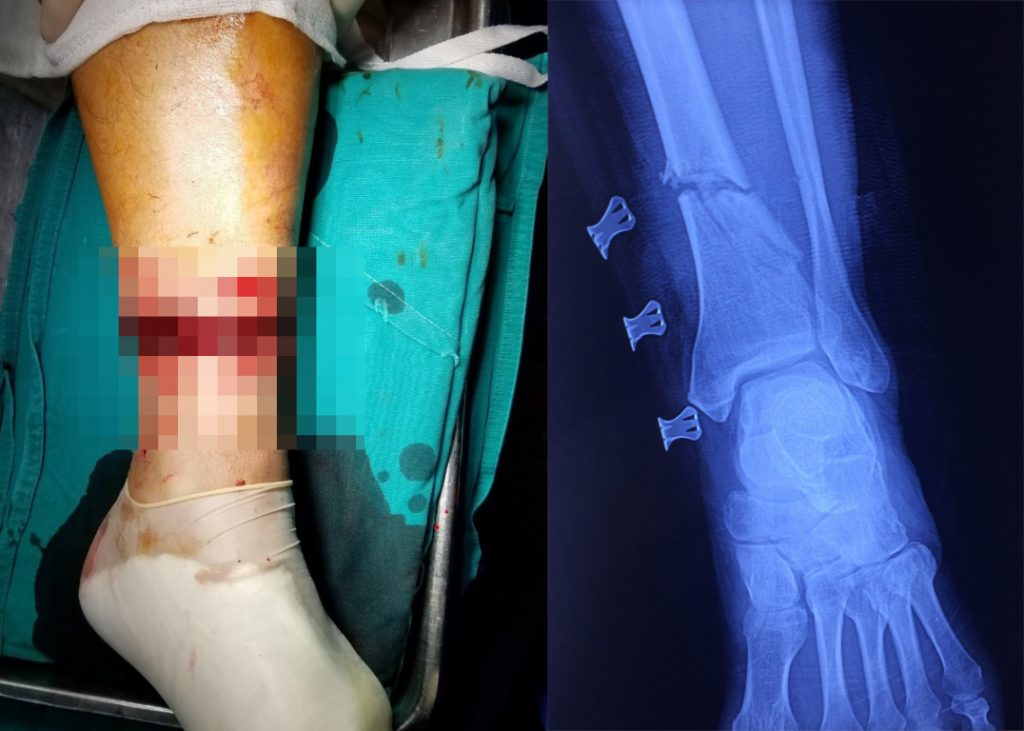

Những hình ảnh thật thương tâm và quá đau lòng khi chứng kiến những vụ tai nạn do những nguy hiểm của lưỡi cắt cỏ gây ra.